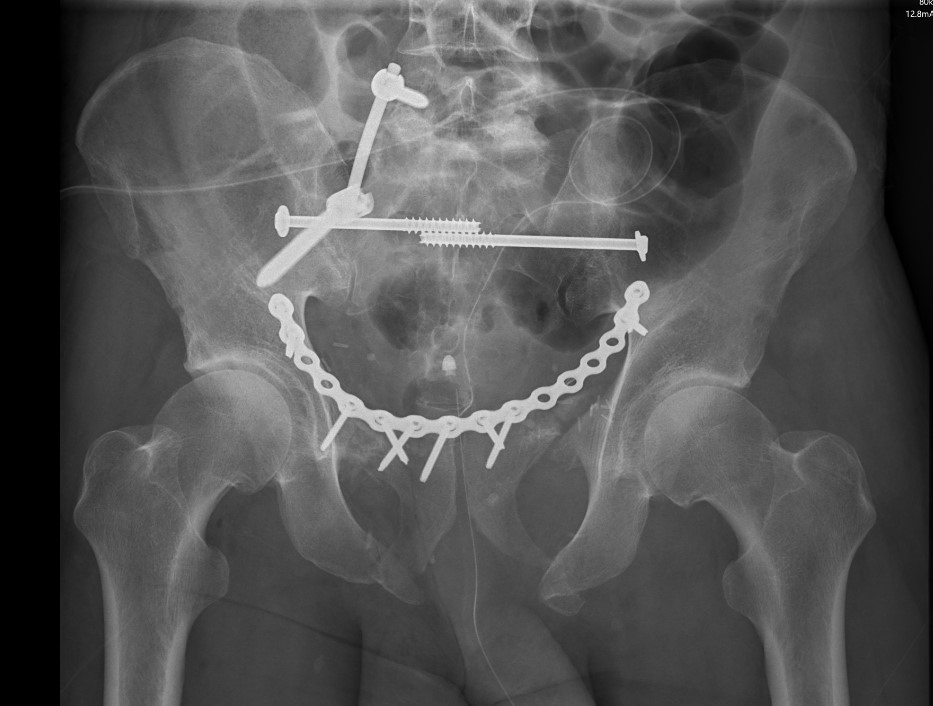

- plate - modified stoppa

LC-1 with anterior external fixation Plating of bilateral pubic rami fractures